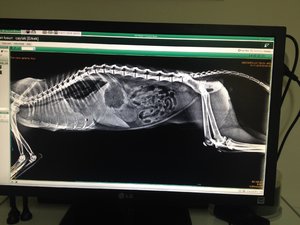

14.11.2016 Zahnwechsel?? Beitrag #29 C caylak Beiträge 32 Reaktionspunkte 0 Es sieht leider sehr schlecht aus Seine lungen sind erweitert... Er hat flüssigkeit in den lungen aber es ist höchst wahrsheinlich kein blut, sonst würde es ihm aus der nase kommen hat der arzt gemeint... Für diese lungen schlaegt er sich richtig tapfer hat er gesagt... Aber viel zu machen sei da nichts... Weiter mit AB und kortisonhaltige tabletten hat er verschrieben bekommen... Wenns schlecht lauft könnte er sogar sterben( Wir sind so fertig.. Es tut richtig weh ihn so zu sehen İch schicke mal das bild der aufnahme.. Vllt könnt ihr ja noch etwas anderes dazu sagen ( Anhänge image.jpg 1,7 MB · Aufrufe: 9

Es sieht leider sehr schlecht aus Seine lungen sind erweitert... Er hat flüssigkeit in den lungen aber es ist höchst wahrsheinlich kein blut, sonst würde es ihm aus der nase kommen hat der arzt gemeint... Für diese lungen schlaegt er sich richtig tapfer hat er gesagt... Aber viel zu machen sei da nichts... Weiter mit AB und kortisonhaltige tabletten hat er verschrieben bekommen... Wenns schlecht lauft könnte er sogar sterben( Wir sind so fertig.. Es tut richtig weh ihn so zu sehen İch schicke mal das bild der aufnahme.. Vllt könnt ihr ja noch etwas anderes dazu sagen (